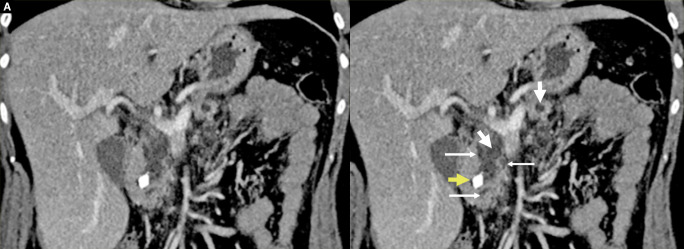

Materials and methods: This is a retrospectively analyzed prospective study conducted at KIMS-Sunshine Hospital, Secunderabad. We evaluated 48 patients who underwent the Frey procedure from 2016 to 2021, each with a follow-up period of at least 1 year. The assessment comprised the validated Izbicki pain score along with evaluations of exocrine and endocrine functions, quality of life using the SF-6 questionnaire, and nutritional status, considering factors such as steatorrhea, glycemic control, and weight gain.

Results: The total number of patients enrolled was 52. Four patients were identified intraoperatively as having malignancy by frozen section and were therefore converted to the Whipple procedure. Therefore, 48 patients (30 = male, 18 = female, mean age 35.2 years) were analyzed in this study. About 6 patients underwent hepaticojejunostomy along with Frey's procedure in view of benign biliary stricture.In this study of 48 patients, the preoperative mean overall pain score was 66.67. Postoperative mean overall pain scores were recorded at 3, 12, 36, and 60 months, showing values of 6.27, 6.37, 8.26, and 8.42, respectively. These results indicate a clear and statistically significant (p < 0.05) reduction in pain both in the immediate and extended follow-up periods.In the first 3 months following surgery, there was weight gain in most of the patients (65%). Though some patients showed mild weight loss subsequently on long-term follow-up, it was not statistically significant (p-value = 0.041).The SF-36 quality of life questionnaire indicated a general improvement in quality of life for the entire group, largely attributable to a reduction in pain. Preoperatively, the mean physical component score (PCS) and mental component score (MCS) were 25.37 ± 6.67 and 26.28 ± 9.94, respectively. These scores increased to 57.78 ± 15.56 and 48.30 ± 26.82 at 3 years, with a p-value of < 0.05.